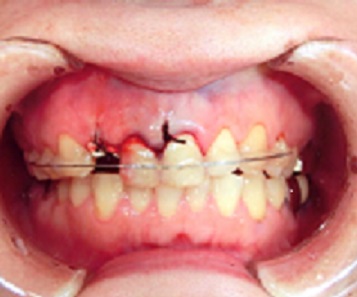

症例1

下顎前歯5本に相当する歯槽骨骨折。

歯牙の変位が著しく、整復し、矯正用器材で固定しました。